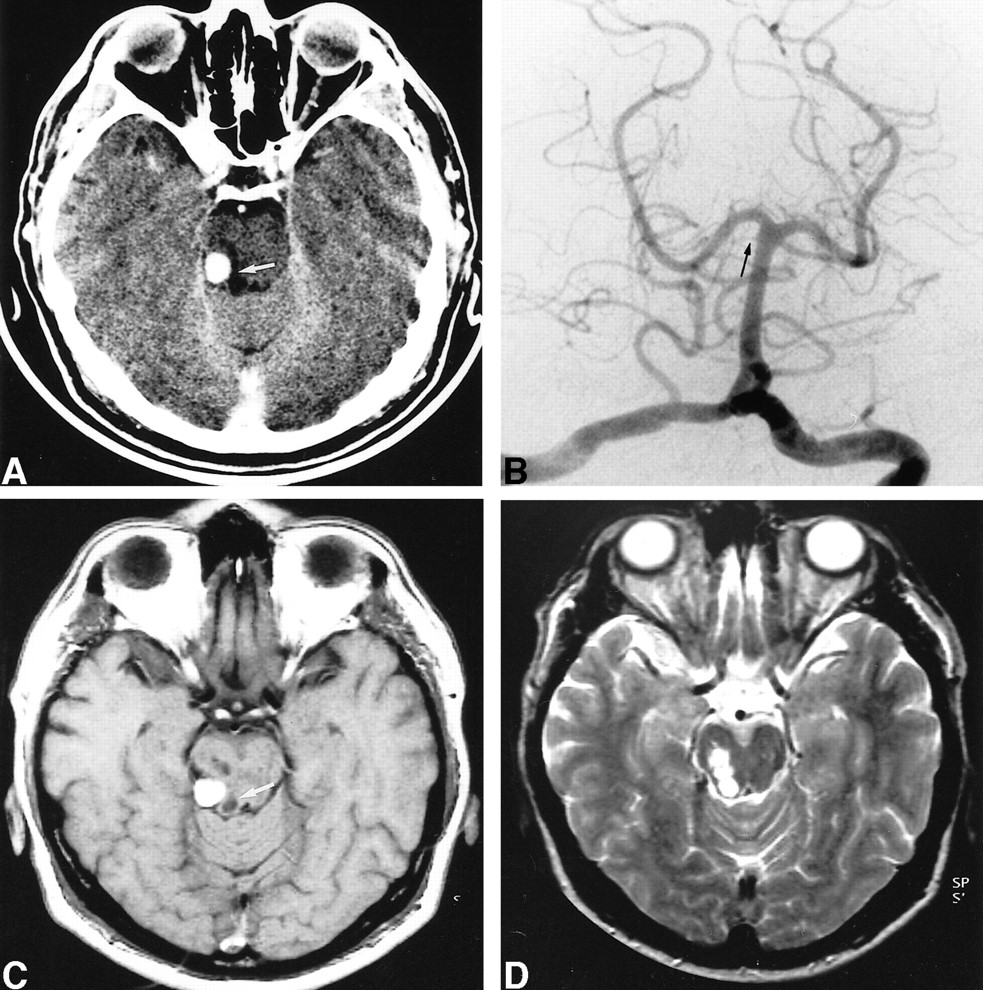

Ten weeks after an uncomplicated delivery, a 27-year-old otherwise healthy woman, with no history of head trauma, had progressive onset of occipital and temporal headache. The day before admission she experienced numbness of the left side of her body, including her face, and slurred speech. Physical examination revealed mild hypoesthesia of the left inferior limb, painful hypoesthesia of the left side of the face, and slight left hyperreflexia. Initial unenhanced and enhanced CT studies showed a well-delineated 1-cm spontaneously hyperdense lesion with minimal enhancement located above the cerebellopontine angle (Fig 1A). There was no evidence of SAH. Hypodense foci suggestive of recent ischemia were visible in the right SCA territory. Left vertebral angiography showed sluggish flow within the right SCA but no aneurysm (Fig 1B). Supraselective injection of the right SCA (Fig 1C) revealed a fusiform aneurysm of the distal hemispheric branch of the SCA with distal occlusion of the branch. Owing to the possibility of spontaneous dissection, with potential risk of rupture, endovascular parent vessel occlusion was elected. A Fastracker-10 double-marker catheter (Target Therapeutics/Boston Scientific, Fremont, CA) was used to catheterize the aneurysm over a 0.010 guidewire (Terumo Corporation, Tokyo, Japan). A 2- × 8-mm Guglielmi detachable soft coil (Target Therapeutics) was delivered partly inside the aneurysm and partly into the parent artery. An immediate control angiogram (Fig 1D) showed total occlusion of the aneurysm and parent artery. The patient's condition improved, including resolution of the headache and of the left-sided hypoesthesia. An MR examination repeated 2 years later (Fig 1E) showed virtually complete disappearance of the aneurysmal mass.

27-year-old woman with progressive onset of occipital and temporal headache.

A, Contrast-enhanced CT scan shows a well-delineated spontaneously hyperdense lesion with minimal enhancement located above the right cerebellopontine angle.

B, Left vertebral selective angiogram (anteroposterior view) shows slow opacification of the right SCA (arrow).

C, Right SCA supraselective injection shows the fusiform aneurysm of a distal hemispheric branch (arrow).

D, Same injection as in C after embolization shows obliteration of the aneurysm along with its parent artery (arrow points to the coil inside the aneurysm).

E, T2-weighted MR image 2 years after treatment shows the low signal intensity of the coil and almost complete disappearance of the mass.